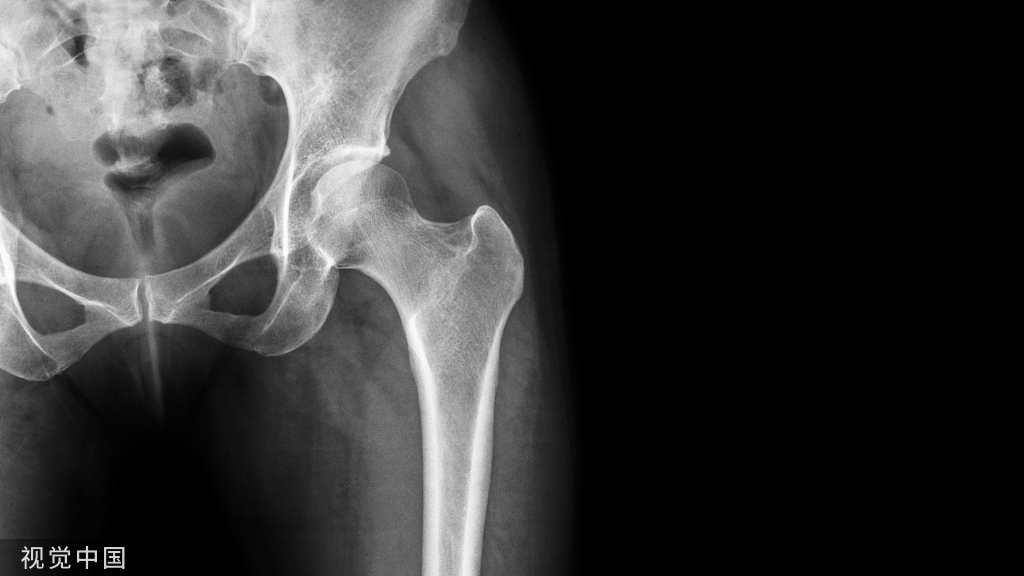

一项调查显示,我国冰雪运动造成中度损伤的发生率约25%—35%。从损伤类型上来说,最常见的类型依次为韧带损伤、软组织擦伤、软组织挫伤和骨折,其中骨折是最严重的损伤。常见骨折部位有腕、踝、膝盖、锁骨肩、腰。这一组数据无疑是在提醒大家,在开展冰雪运动之时,一定要绷紧安全之弦。

滑雪过程中摔伤骨折应该怎么办?

1、对于四肢骨折而言,我们应该进行妥善地对受伤处进行固定,固定的范围应该在骨折处与邻近的两个关节。以前臂骨折为例,在我们固定前臂的时候,同时要固定相邻的腕关节和肘关节。在户外进行固定时,可以就近取材,比如可以使用树枝、木棍等。

骨科医生强调:固定时不要将这些固定物直接接触皮肤,防止硬物压伤。固定后,如果发现,手指脚背等地方出现苍白、肢体发凉、青紫、疼痛麻木的症状说明绷得太紧,造成血液循环不良,此时应重新固定。

2、对于脊柱骨折,周围多人可以合力平托病人,稳稳当当将其放在门板或木板上;或者人员比较少不足以抬动患者,可以使患者保持仰卧位,整体呈一轴线滚动到木板上,千万不要随意搬动,造成二次损伤。

3、颈椎骨折或者脱位,需要另外一人牵引固定头部,并与身体保持一致,同步搬运。颈椎两侧用折好的物品或者沙袋加以固定。

4、严重骨折会导致休克,危及生命,需要寻求专业人员紧急进行抗休克处理,就医治疗。如果伴有颅脑复合伤而处于昏迷中的患者,应保持呼吸道通畅,避免周围人群围观,造成环境缺氧。